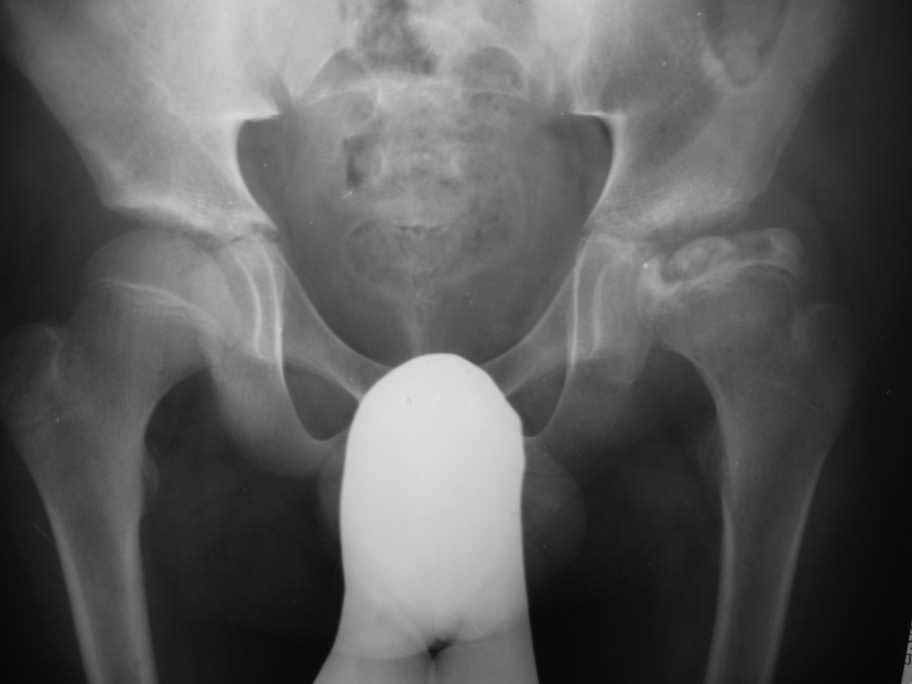

Здравствуйте уважаемые коллеги,Посоветуйте, пожалуйста, тактику лечения для пациента с болезнью Пертеса.

Мальчик 14- ти лет обратился с жалобами на боли в левом тазобедренном суставе. Болеет около шести месяцев

Клинически : Движения в суставе ограничены ,сгибание 90 гр, отведение -30гр,ротационные движения 5-0-5 гр.Спасибо Ihor

Уважаемый Ihor! Если внимательно присмотреться на ацетабулярный край ( место прикрепления губы) слева, то вы увидите результат конфликта инконгруэнтности (hinge abduction- шарнирное отведение), при отведении больше 15-20 градусов часть головки, в буквальном смысле, упирается в край впадины и дальнейшее отведение происходит уже с центром ротации в этой точке ( именно поэтому шарнирное отведение). Представим, что тройной остеотомией таза мы "горизонтализируя" , "перекрывая" (изв. за слэнг) головку на 15 град. вызовем конфликт уже при отведении 0-5 градусов.Надежды на ремоделяцию в 14 лет ничтожны.

Эта проблема решается или вальгизирующей остеотомией (дополнительный доступ) или resection osteochondroplasty после капсулотомии при выполнении тройной остеотомии таза. Дислокация бедра по Ганцу (Бернская) Ganz Bernese hip dislocation может быть как этап подготовки к реориентации впадины тройной остеотомией таза (Acetabular Osteochondroplasty and Simultaneous Reorientation: Background and Validation of Concept by Lucas A. Anderson, PA-C; Carmen D. Crofoot, MD; Jill Erickson, PA-C; David A. Morton, PhD; Christopher L. Peters, MD), но не думаю что в этом случае надо вмешиваться на впадине. По поводу ШДУ : справа и больше слева снимок выполнен с наружной ротацией бедра (малый вертел "торчит")поэтому вальга проекционная.